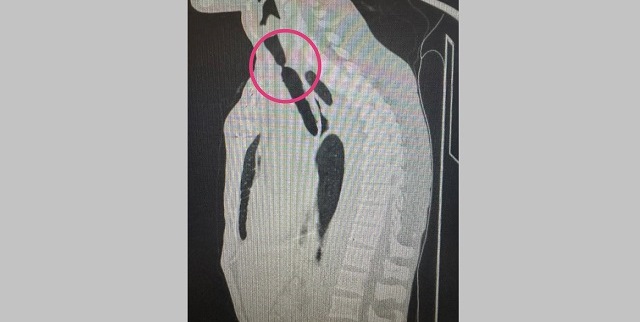

Врачи пояснили, что 10 лет назад 48-летний мужчина попал в ДТП и долгое время находится на искусственной вентиляции легких. Из-за стеноза просвет трахеи был всего четыре миллиметра.

Торакальный хирург Константин Шкляев и бронхолог Фанис Нурмиев провели эндоскопическую реканализацию трахеи и стентирование трахеи. Место сужения расширилось до 20 миллиметров. Раньше на стентирование врачи отправляли в федеральный центр.